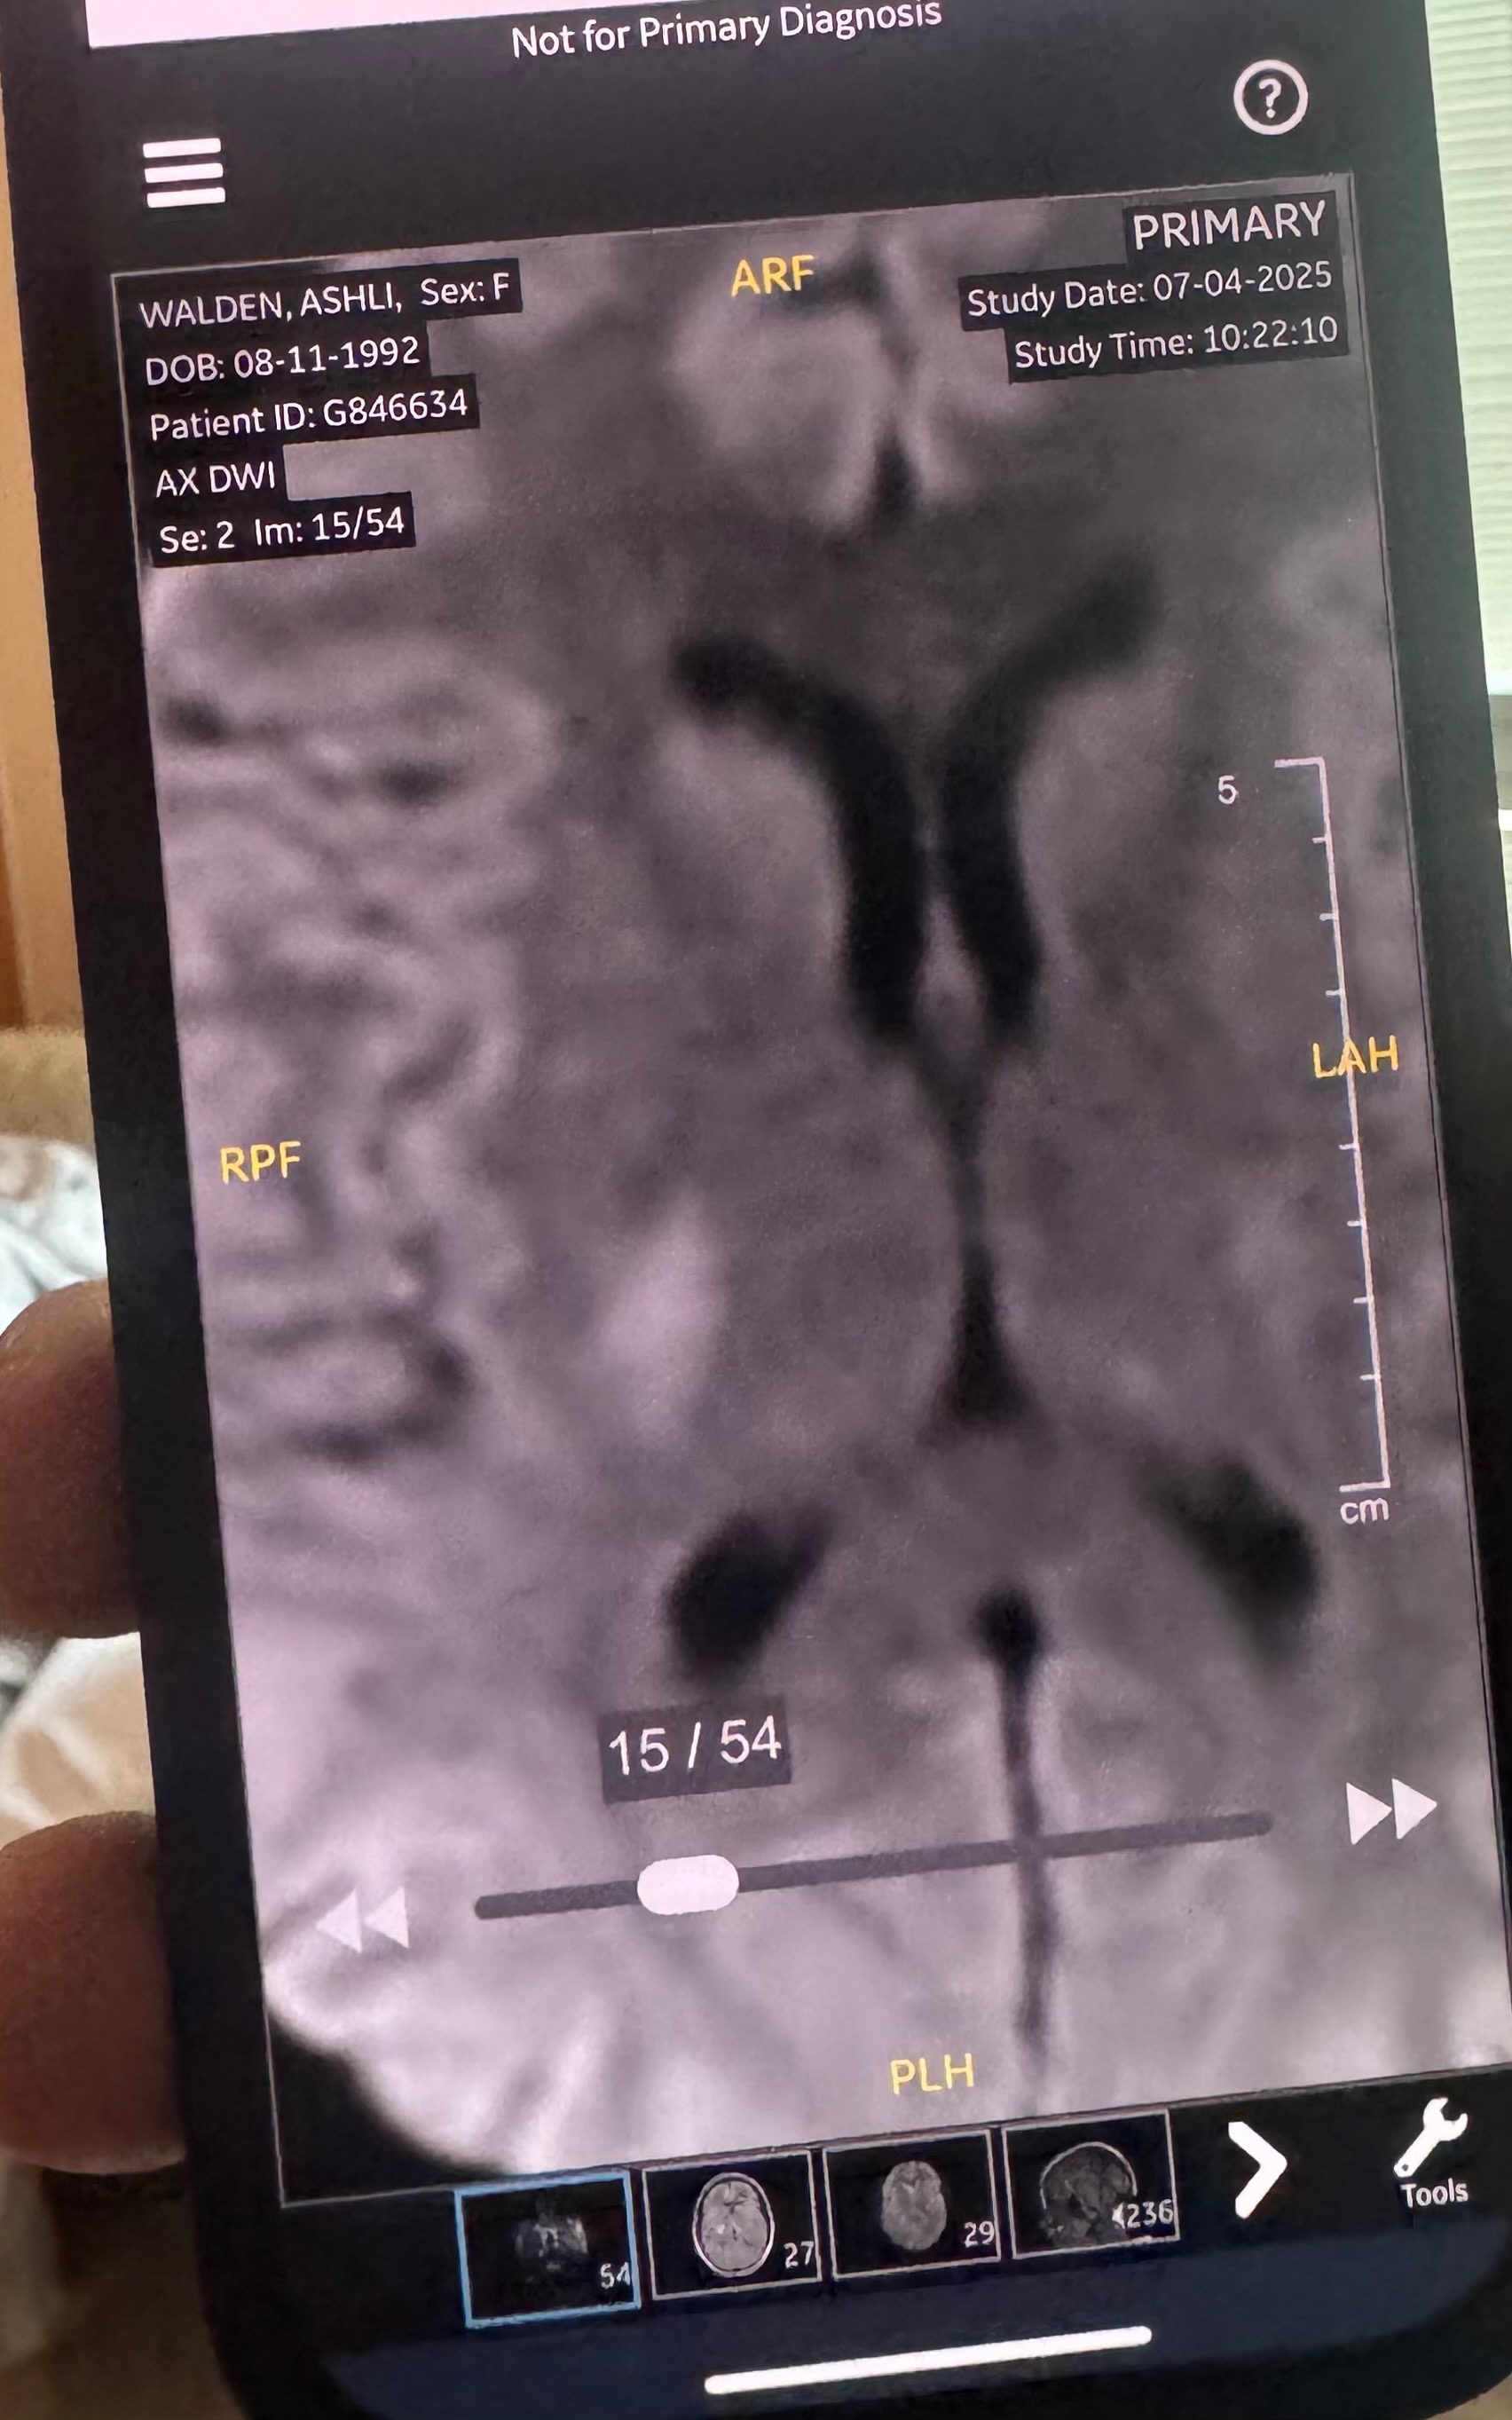

- This stroke has affected her right basal ganglia. A stroke in the right basal ganglia can cause a range of neurological issues, including movement disorders, emotional and cognitive impairments, and difficulties with spatial awareness and perception. Specifically, damage to the right basal ganglia can lead to left-sided neglect, making it difficult to recognize or respond to stimuli on the left side of the body and environment. Other potential effects include apathy, slowed or reduced movement, memory problems, and emotional blunting. Physical therapy will be required to gain strength back in her left side. This has also had an impact on cognition. She’s currently unable to fully read or understand text messages and struggles to form a response back via text. She is able to understand physical language, so a phone call or video call is best right now.